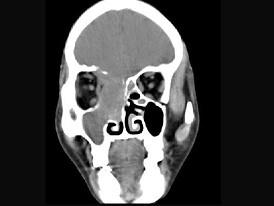

女性,53岁,右侧鼻腔流血近一年,近来头痛,行CT检查如图所示,请选择正确的答案 ( )

• A.鼻腔内血管瘤

• B.鼻腔内息肉

• C.鼻腔癌

• D.鼻腔炎性假瘤

• E.副鼻窦炎

答案: C